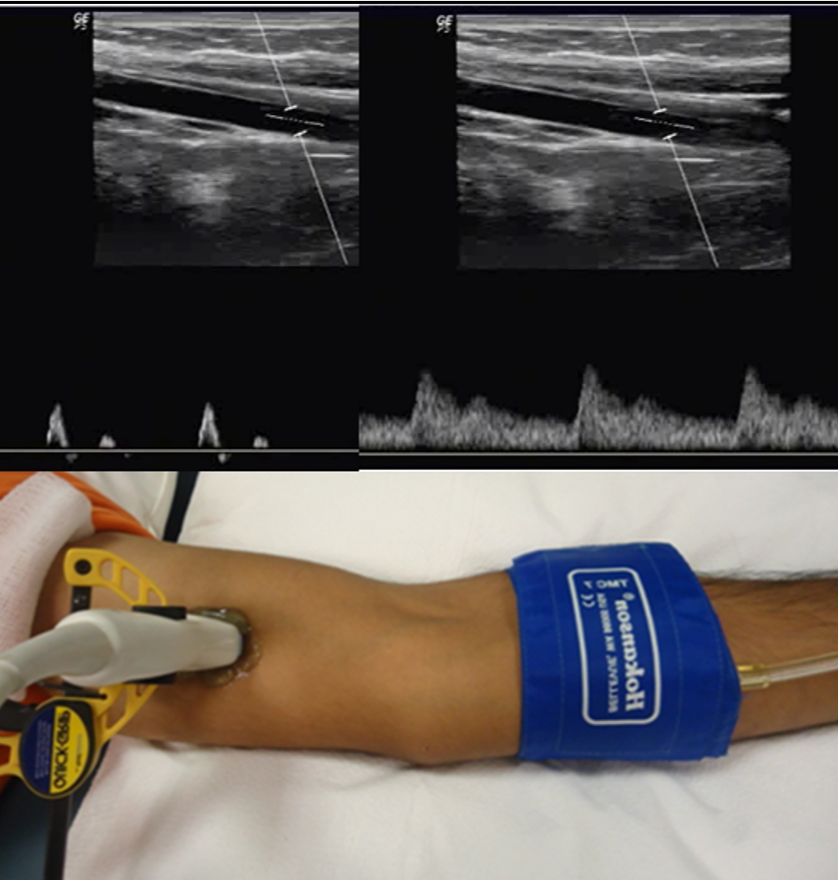

We use sonography to measure brain blood flow non-invasively.

Nervous System Function

We use ultrasound-guided microneurography to measure sympathetic nervous system activity directly.